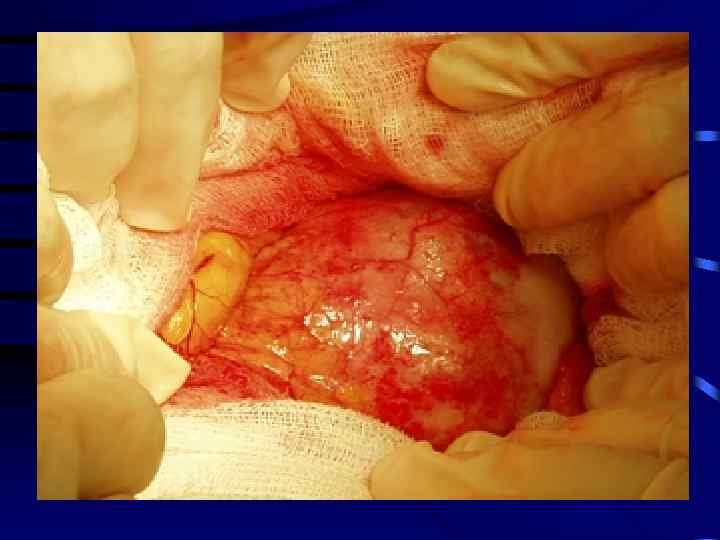

Врожденные кисты (цистаденомы) • возникает из врожденного остатка или нормального пролиферированного эпителия мелких протоков • в течение всей жизни могут быть бессимптомными • выявляются чаще у женщин среднего и пожилого возраста в связи с ростом кисты и появлением клинической симптоматики. • Возможно перерождение в цистаденокарциному

Клиника и диагностика • Клиника возникает при значительных размерах кисты: чувство тяжести, боль, диспепсия, пальпируемое образование в проекции поджелудочной железы • Диагностика – УЗИ, КТ, МРТ поджелудочной железы. • Лечение – удаление кисты (экстрапанкреатически расположенной), либо резекция поджелудочной железы с кистой.